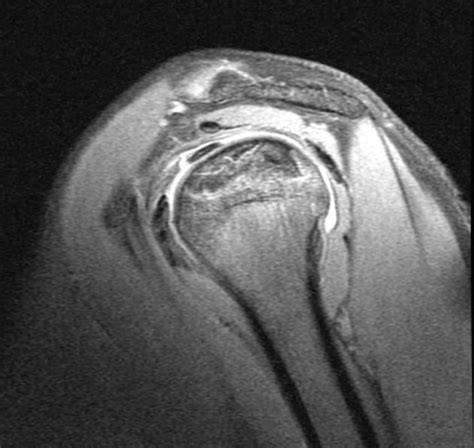

Since the condition often starts invisibly, physicians use advanced imaging to confirm the presence of bone death. X-rays are typically the first line of defense, though they often fail to show early-stage damage. An MRI scan is widely considered the gold standard for diagnosing avascular necrosis, as it can detect changes in the bone marrow before the structure of the bone actually changes.

💡 Note: While MRI is highly sensitive, it should always be interpreted alongside a physical examination to ensure that the findings correlate with your specific pain patterns.

| Shoulder | Deep pain in the upper arm | Reduced range of motion for reaching |